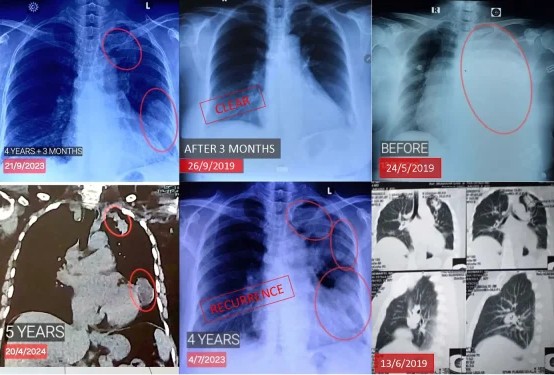

The Miracle of the Vanishing Tumor: Clear in Just 3 Months

Beating Adenocarcinoma Twice Without Chemotherapy or Biopsy

In 2017, Bu Soewarti was diagnosed with lung cancer marked by a 4cm tumor and severe coughing of blood. Fearing the side effects of conventional medicine and her advanced age, she refused chemotherapy and biopsy, opting instead for ECCT (Electro-Capacitive Cancer Therapy). The response was unprecedented: within just three months of wearing the device, the tumor mass completely disappeared on CT scans, and she stopped treatment. Although the cancer reactivated four years later following a vaccination and years of inactivity, resuming the device quickly brought her condition back under control, allowing her to survive well beyond the initial 5% survival rate for her condition.